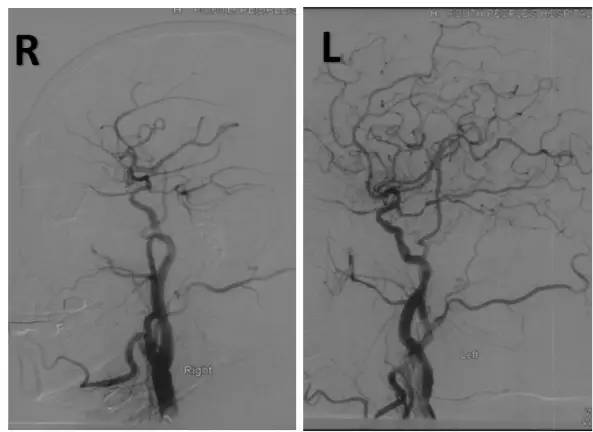

全麻下右股动脉穿刺置入6F动脉鞘,将6F导引导管至右椎动脉V1段,造影:右椎动脉V2段近段及远段狭窄。右椎动脉V4闭塞,右椎动脉V4远段经由脊髓前动脉代偿显影,左椎动脉由对侧椎动脉肌支及脊髓前代偿部分显影(图8)。

图8